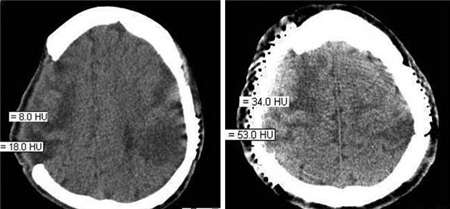

脑外伤后遗症是一种致残率高、死亡率高的疾病,它的出现常常使患者出现癫痫、失语、失用等症状,甚至给患者的生命安全带来隐患。目前随着脑外伤后遗症患者的增多,脑外伤后遗症已经成为一种影响人类健康的重大疾病。因为,详细了解脑外伤后遗症的早期症状,能够及早发现疾病、及早采取防范性的治疗。

脑外伤后遗症患者除了会出现瘫痪、失语、痴呆、头痛、易怒、注意力不能集中、记忆力下降、头晕、失眠等症状,有些还会生活不能自理,甚至有的患者成为了植物人。

而脑外伤后遗症还存在一个不同时间的潜伏期,所以及时科学有效的治疗尤为重要。专家表示:脑外伤后遗症如果不能得到及时有效治疗,易给患者造成终身遗憾,所以患者在发现上述脑外伤后遗症的症状后,一定要及时做到早发现、早治疗。